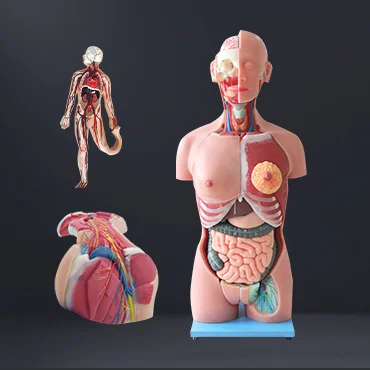

Zhengzhou Meiwo Science & Technology Co., Ltd established in 2009, is a comprehensive technology enterprise for medical education integrating R&D, production and sales. Meiwo Science has independent specimen production workshops and model production workshops covering an area of 10,000 square meters. Meiwo main products involve plastinated animal specimens, soft silicone anatomy models, high simulation soft anatomy models, human & animal anatomy softwares, 3D digital human specimen, biological microscope slides, animal skeletons, etc.

What we offer: